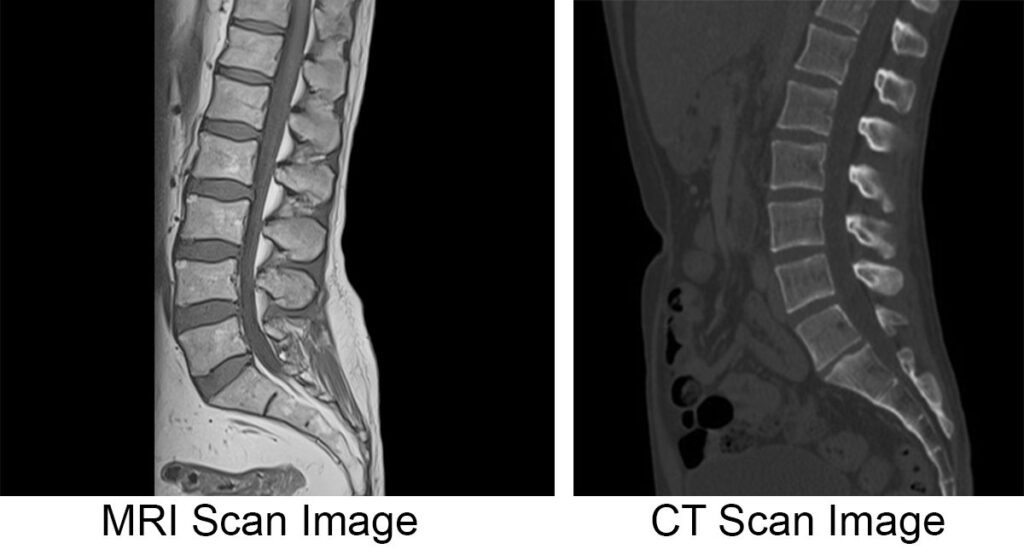

CT scans and MRI scans serve different diagnostic purposes, each excelling in specific areas of medical imaging. While both create detailed internal body images, CT technology offers unique advantages for certain conditions and anatomical structures.

CT scans provide exceptional bone detail that MRI cannot match. The technology excels at detecting fractures, bone infections, and structural abnormalities within skeletal systems. Small hairline fractures often invisible on MRI become clearly visible through CT imaging.

Despite its advantages, CT scanning cannot match MRI’s soft tissue contrast resolution. Brain and spinal cord imaging often requires MRI for detailed evaluation. Cartilage, ligaments, and tendons appear more clearly on MRI examinations.

Each technology provides different information. CT may show bone involvement while MRI reveals soft tissue extent of the same condition.